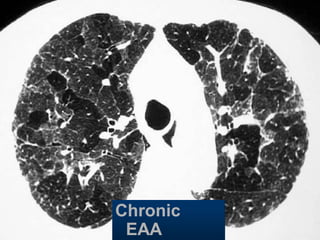

Chronic

EAA